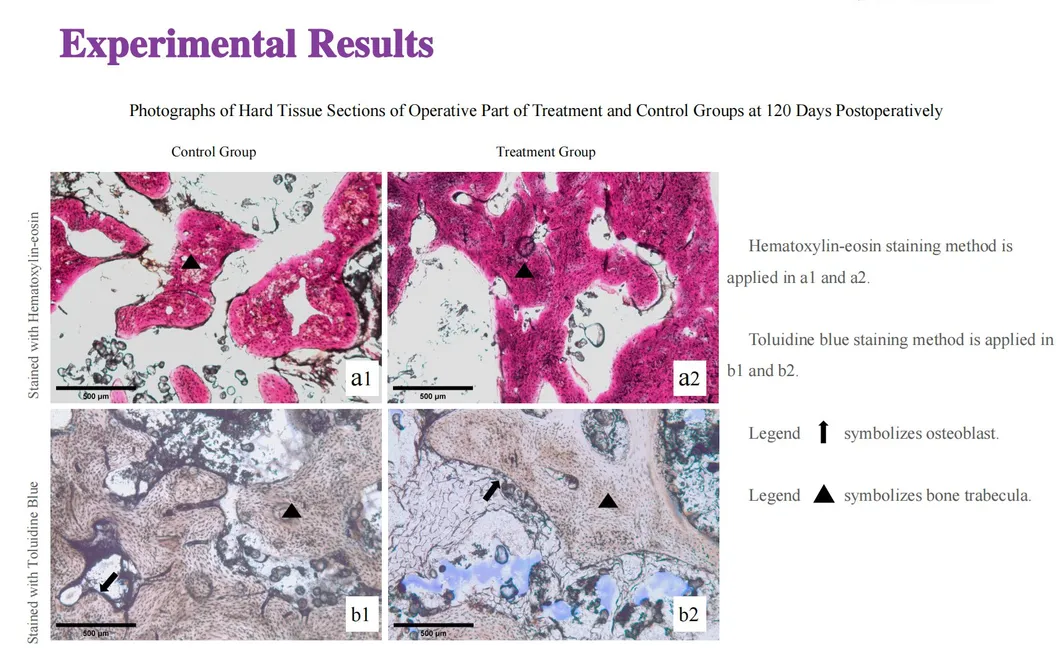

This study evaluated the effectiveness of state-of-the-art dental tools for veterinary use. The treatment group utilized the revolutionary Pneumatic Dental Elevator Kit. Critical factors observed included physiological parameters, intraoperative complications, extraction duration, and socket damage. Rigorous statistical analysis highlights the superior performance of these advanced tools.